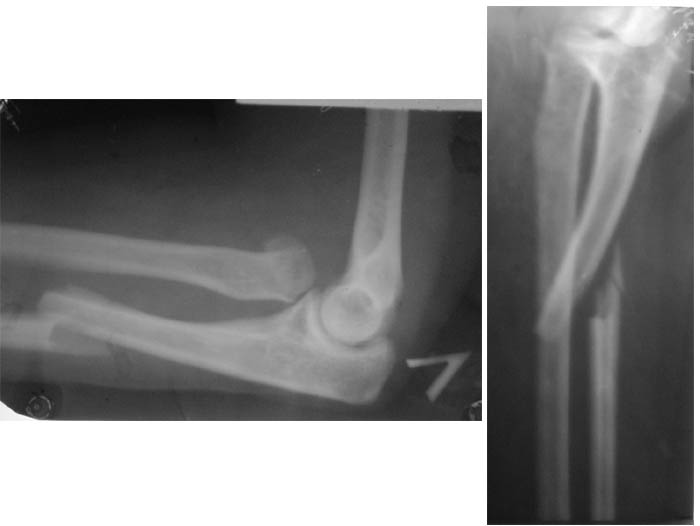

Уважаемые коллеги! Больная, 28 лет. Сутки назад получила травму (см.), сопут. - эпилепсия (инвалид 2 группы с 16 лет).

Больная поступает в ургентом порядке. Какова ваша тактика в подобном случае?Заранее благодарю! С уважением,А.В.Владзимирский

Перелом Монтеджи. Лечить следует оперативно, консервативная тектика при такой травме неприменима из-за повреждения связки на головке лучевой кости и невозможности удержания её консервативными методами. Необходим остеосинтез локтевой кости (штифт, пластина) и резекция головки лучевой кости.

Во-первых повреждение Монтеджи плюс перелом шейки лучевой кости.Возможна первичная закрытая репозиция с фиксацией головки и шейки спицей через головочку мыщелка с послед. фиксацией гипс. лонгетой.При неудаче отсроченная открытая репозиция головки луч. кости с фиксацией спицей, если не произошла репозиция локт. кости, открытый остеосинтез кости пластиной.Резецировать головку по данной рентгенограмме нет необходимости, хотя окончательное решение нужно принимать интраоперационно.